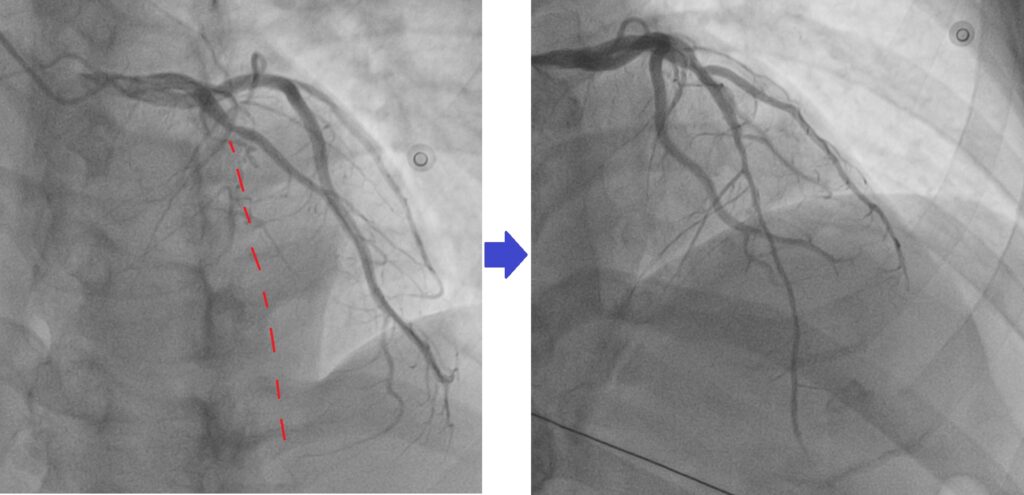

随着技术进步,现在许多 CTO 也可以通过心脏血管介入治疗来打开血管。

在 CTO PCI 手术中,医生会:

- 从手腕或腹股沟血管放入导管

- 使用特殊导丝穿过堵塞的血管

- 用气球扩张血管

- 放置支架保持血管畅通

在经验丰富的中心,CTO PCI 的成功率可以达到 85–90% 以上。